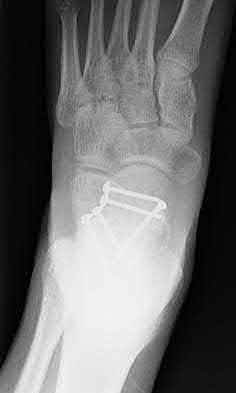

Figure A shows a patient after an open reduction and internal fixation of a bimalleolar ankle fracture.

Egol et al showed that by nine weeks, the total braking time of patients who had undergone fixation of a displaced right ankle fracture returns to the normal, baseline value.

Egol et al, also found that appropriate braking time returns at a point 6 weeks after initiation of weightbearing after treatment of lower extremity long bone and periarticular fractures, as examined with a driving simulator. No differences were seen in return of braking time between periarticular fractures and long bone injuries.